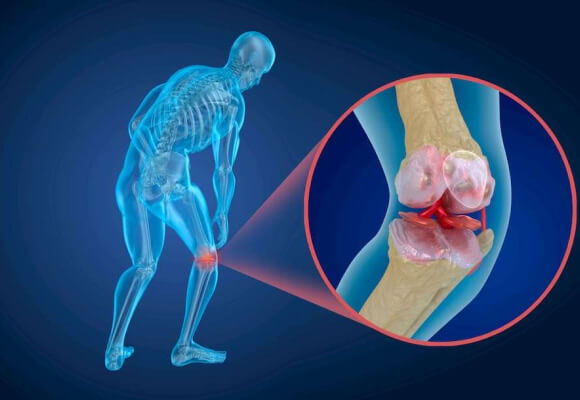

Rahasianya adalah dengan memahami mengapa Anda merasakan nyeri. Secara keseluruhan terdapat hingga 147 kemungkinan alasan yang berbeda sebagai penyebab berkembangnya osteokondrosis dan radang sendi yang tercantum di ensiklopedia ilmiah tentang tubuh manusia, tetapi konsekuensinya hanya ada satu – sendi, tulang belakang dan tulang rawan kehilangan elastisitasnya, karena itulah muncul rasa sakit. Sendi, tulang belakang dan tulang rawan rusak karena sirkulasi darah yang buruk.

Ya, tentu saja, dan bukan hanya sekali dua kali saja. Namun demikian, kebanyakan pasien saya memang orang–orang biasa yang berusia di atas 40 tahun yang mulai menderita penyakit-penyakit ini seiring bertambahnya usia mereka. Mereka datang kepada saya dengan masalah-masalah yang sama: osteokondrosis, radang sendi, radikulitis, dan saraf terjepit. Penyakit-penyakit ini sangat mengganggu dan tidak membiarkan hidup dengan normal.

Tidak, itulah yang berusaha saya jelaskan: produk ini bekerja pada tingkat sel, memulihkan aliran darah Anda. Produk ini membantu menghilangkan banyak penyakit yang terkait dengan sendi dan tulang belakang: artrosis dan radang sendi, linu panggul, rematik, radikulitis, hernia tulang belakang. Cedera, trauma, memar, patah tulang, bahkan kapalan – krim sangat efektif dalam semua kasus ini.